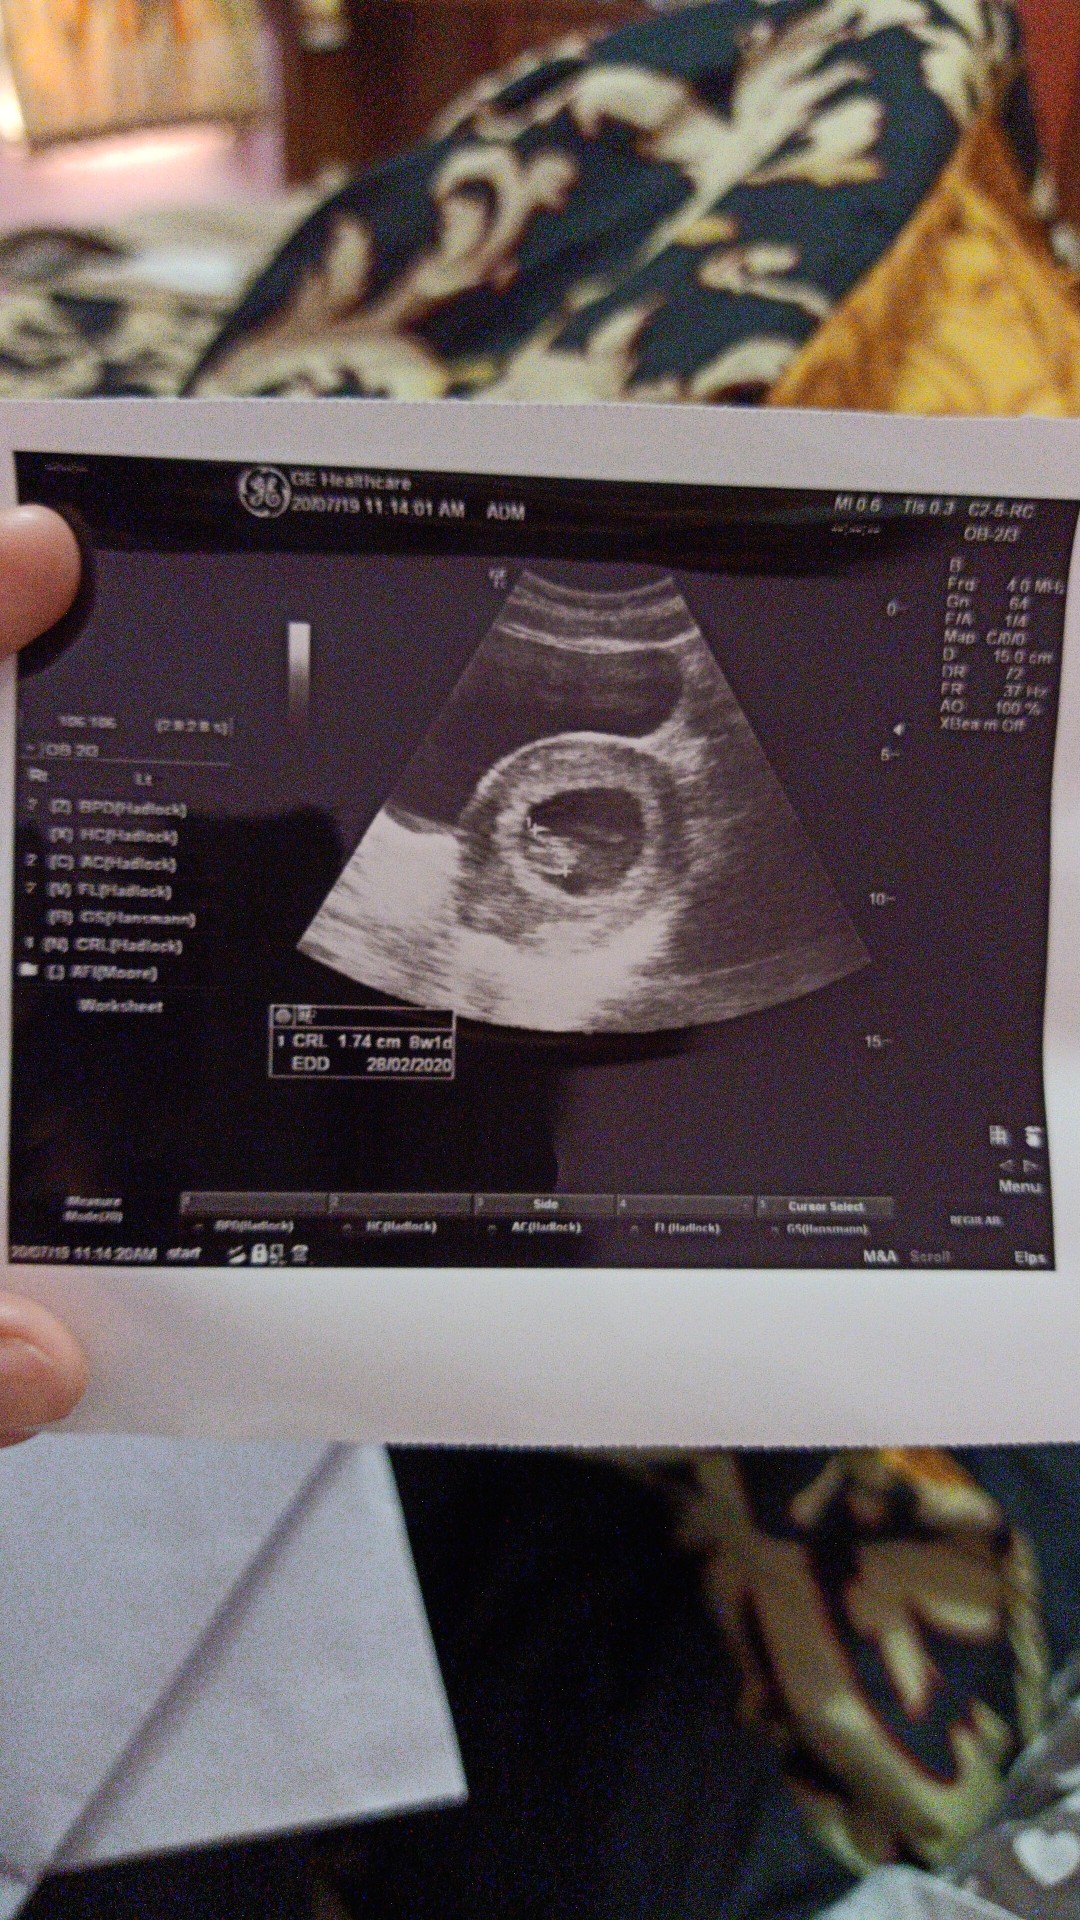

Ini hasil usg saya bun pas 8w1d. Alhamdulillah janin sudah keliatan terus djj juga sudah terdengar bunda 💕 Barakallah